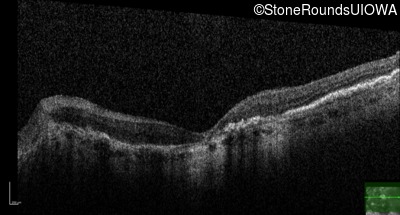

Age at visit: 64 years

This 64 year old woman first noticed some distortion in her vision at age 46 while looking at graph paper.